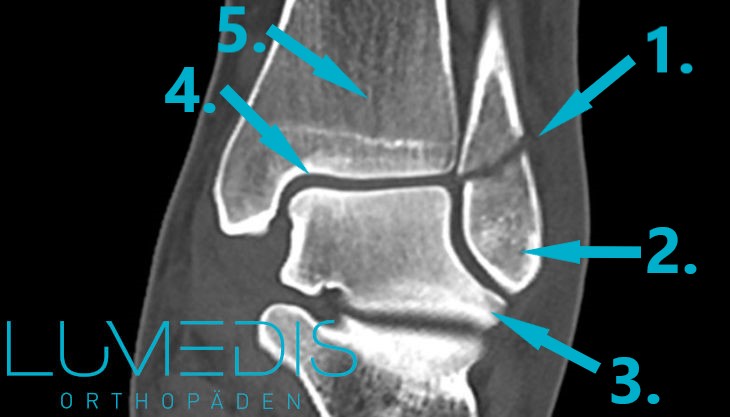

CT einer Weber B-Fraktur

CT Rekonstruktion einer bimalleolären Fraktur des oberen Sprunggelenks

CT-Rekonstruktion einer Weber B-Fraktur